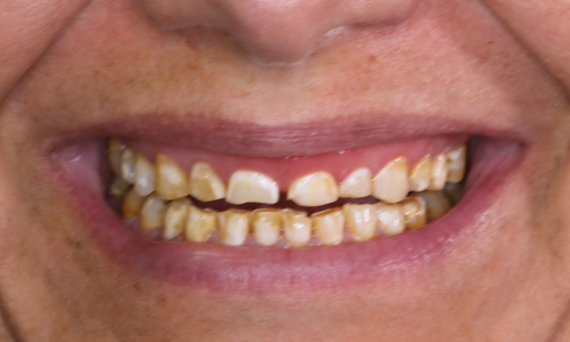

Before

Patient, dissatisfied with her smile due to tooth discoloration.

After

Ten highly esthetic single crowns, individualized with stains.